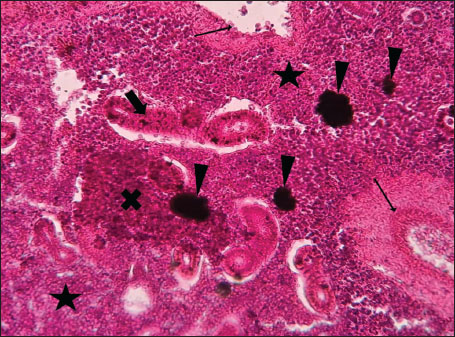

ABSTRACTBackground: The Mediterranean Sea has undergone significant ecological changes in recent decades, partly due to the introduction of non-native species. Lagocephalus sceleratus is an invasive Lessepsian species widely distributed in the Mediterranean, increasingly abundant along the Libyan coast, and potentially exposed to chronic environmental stressors. This species represents an important model for baseline pathological assessment in newly colonized marine environments. Aim: This study provides a descriptive histopathological assessment of kidney and gill tissues in adult L. sceleratus to document baseline tissue alterations without inferring direct environmental or pollution-related causation. Methods: A total of 150 adult specimens were collected from four Libyan coastal locations. Tissues were processed using standard histological techniques and evaluated semi-quantitatively (+, ++, +++) for lesion severity. Lesion severity grades were converted into ordinal numerical data and summarized using descriptive statistical approaches only. Results: Kidney tissues exhibited tubular degeneration, Bowman’s capsule dilatation, vascular congestion, extensive melanomacrophage centers (MMCs), and inflammatory lesions. Gill tissues showed disorganization of secondary lamellae, epithelial hyperplasia, edema, aneurysmal dilatations, vascular congestion, and MMC proliferation, some of which were associated with histologically observed parasitic structures. Conclusion: The observed alterations represent descriptive baseline tissue changes and should not be interpreted as direct evidence of pollution or specific environmental stressors. These findings provide reference data for future comparative pathological and ecological studies. Keywords: Lagocephalus sceleratus, Kidney, Gills, Histopathology, Melanomacrophage centers, Invasive species, Mediterranean Sea. IntroductionIn recent decades, the Mediterranean Sea has undergone profound ecological changes driven by the arrival and establishment of non-native marine species. Among these, Lagocephalus sceleratus has emerged as one of the most impactful Lessepsian migrants, due to its rapid geographic expansion, high ecological adaptability, and the presence of the potent neurotoxin tetrodotoxin in its tissues. This species has been widely documented to alter local fish communities, affect fisheries, and pose public health risks, making it an important target for biological and environmental assessment across the region (Katikou et al., 2022; Christidis et al., 2024). Fish are widely recognized as sensitive biological organisms in aquatic ecosystems, particularly in coastal habitats that are exposed to anthropogenic pressures such as industrial effluents, agricultural runoff, and untreated wastewater (Pinna et al., 2023). Among fish organs, the gills and kidneys are commonly regarded as sensitive to environmental stress, as they respond to physiological and pathological changes under environmentally suboptimal conditions. The gills, due to their large surface area and continuous exposure to surrounding water, are often the first tissues to exhibit structural alterations when fish encounter pollutants (Shahid et al., 2022). Histopathological changes in gills observed in polluted environments include epithelial lifting, lamellar fusion, hyperplasia, increased mucous cell density, and focal necrosis, which collectively reflect early physiological stress and potential compromise of respiratory function (Osman, 2010; Shahid et al., 2022). Similarly, the kidneys play crucial roles in osmoregulation, excretion of metabolic waste, and detoxification, making them highly vulnerable to chronic or systemic toxic effects (Wahidi et al., 2025). Documented renal lesions associated with chemical exposure include tubular deterioration, glomerular shrinkage, interstitial edema, and infiltration of inflammatory cells. These structural alterations often coincide with underlying biochemical disruptions, such as oxidative stress, impaired detoxification pathways, and activation of apoptotic mechanisms (Bernet et al., 1999; Authman, 2015). Despite the growing body of research on the ecological and toxicological implications of L. sceleratus, detailed histopathological assessments of this species remain scarce, especially in the southern Mediterranean basin, where environmental conditions and pollution profiles may differ from those in other regions. To date, detailed tissue-level studies of L. sceleratus from the southern Mediterranean are lacking, which limits the understanding of how this invasive species responds physiologically to local environmental stressors (Shakman et al., 2019; Ulman et al., 2021; Mohmmed et al., 2023). Accordingly, the present study aims to provide a comprehensive descriptive evaluation of histopathological changes in the kidneys and gills of L. sceleratus. The study is designed as a baseline histopathological assessment, focusing on tissue-level alterations without establishing causal links to environmental pollution or physicochemical stressors. By documenting structural aberrations and pathological features, this study contributes reference data for future monitoring and comparative studies in Mediterranean coastal ecosystems. Materials and MethodsSample designA total of 150 adult specimens of L. sceleratus, including both sexes, were collected from four Libyan coastal locations: Talamitha (n=39), Susah (n=34), Ain El-Ghazala (n=30), and Khalij Al-Bambah (n=47). Fish ranged in total length from 51 to 66 cm and in weight from 1.5 to 3.5 kg. Only apparently healthy adults were included, while juveniles were excluded to avoid age-related histopathological variation. Sampling was conducted opportunistically with assistance from local fishermen. All specimens were collected within a comparable seasonal window to minimize seasonal histopathological variability. Sex was recorded when possible; however, sex-based histopathological comparisons were not performed, as this was beyond the descriptive scope of the study. Fish were transported on ice at +4°C and examined in the Pathology Laboratory, Faculty of Veterinary Medicine, Omar Al-Mukhtar University (Mohmmed et al., 2023). Specimens were collected from a range of depths (0.5–70 m), with the majority from shallow waters (<10 m) and a subset (approximately 50 fish) from deeper locations (>30 m). Environmental physicochemical parameters such as temperature, salinity, and dissolved oxygen were not measured; therefore, no direct associations between histopathological findings and environmental variables were assessed. Tissue processing and histopathological examinationTissue specimens were fixed in 10% neutral buffered formalin for 24 hours. Following fixation, the samples were transferred to 70% ethanol for storage at room temperature. Subsequently, the tissues were processed for routine histopathological examination following standard procedures (Paul and Chanda, 2017). Paraffin embedding was performed, and 5 µm-thick sections were prepared using a microtome. Sections were stained with hematoxylin and eosin (H&E) and examined under a light microscope. Photomicrographs of representative lesions were captured using a high-resolution digital camera. Histopathological alterations were evaluated using a semi-quantitative scoring system adapted from Hose et al. (1996), Moshaie-Nezhad et al. (2021), and Alshailabi et al. (2023), where lesion severity was graded as mild (+), moderate (++), or severe (+++). Lesion severity grades (+, ++, +++) were converted into ordinal numerical values (1–3) for descriptive summarization of lesion severity. Due to the descriptive baseline nature of the study and the absence of a reference control group, inferential statistical comparisons were not emphasized or applied. Lesion severity scores were therefore summarized descriptively to avoid overinterpretation of the findings. Scoring was performed independently by two experienced observers, and representative lesions were confirmed across three sections per organ to ensure consistency. Tissues with visible parasitic structures were described separately from non-parasitized tissues to avoid conflating parasite-associated lesions with non-specific tissue alterations. The functional implications of the observed lesions were interpreted in accordance with Flores-Lopes and Thomaz (2011). Ethical approvalAll animal experiments conducted in this study were approved by the Ministry of Higher Education & Scientific Research and the Libyan National Committee for Biosafety & Bioethics, Libya. All procedures were performed in accordance with the relevant ethical guidelines, with session number 21/CH/25, dated 26/05/2021. ResultsHistopathological examination of the kidneyHistopathological examination of the kidney tissues of L. sceleratus revealed multiple alterations. Prominent melanomacrophage centers (MMCs), necrotic areas, dilatation of Bowman’s capsules, and vacuolar degeneration were observed (Fig. 1), associated with interstitial lymphohematopoietic tissue (Fig. 2). Dilated and congested blood vessels and extensive MMCs were also noted (Fig. 3). Renal degeneration surrounding lymphohematopoietic tissue, large clusters of MMCs, and thickened, congested vessel walls within fibrotic areas were evident (Fig. 4). Atrophic renal degeneration with necrotic and vacuolar changes was observed (Fig. 5). Severe inflammatory infiltration of lymphatic cells and granulomas with necrotic centers, surrounded by fibrous tissue, was detected (Figs. 6–7).

Fig. 4. Histopathology of the kidney in an adult L. sceleratus showing renal degeneration surrounding lymphohematopoietic tissue (stars), large MMC clusters (head arrows), and congested, dilated, thickened vessel walls within fibrotic areas (thin arrows). ×400 H&E.